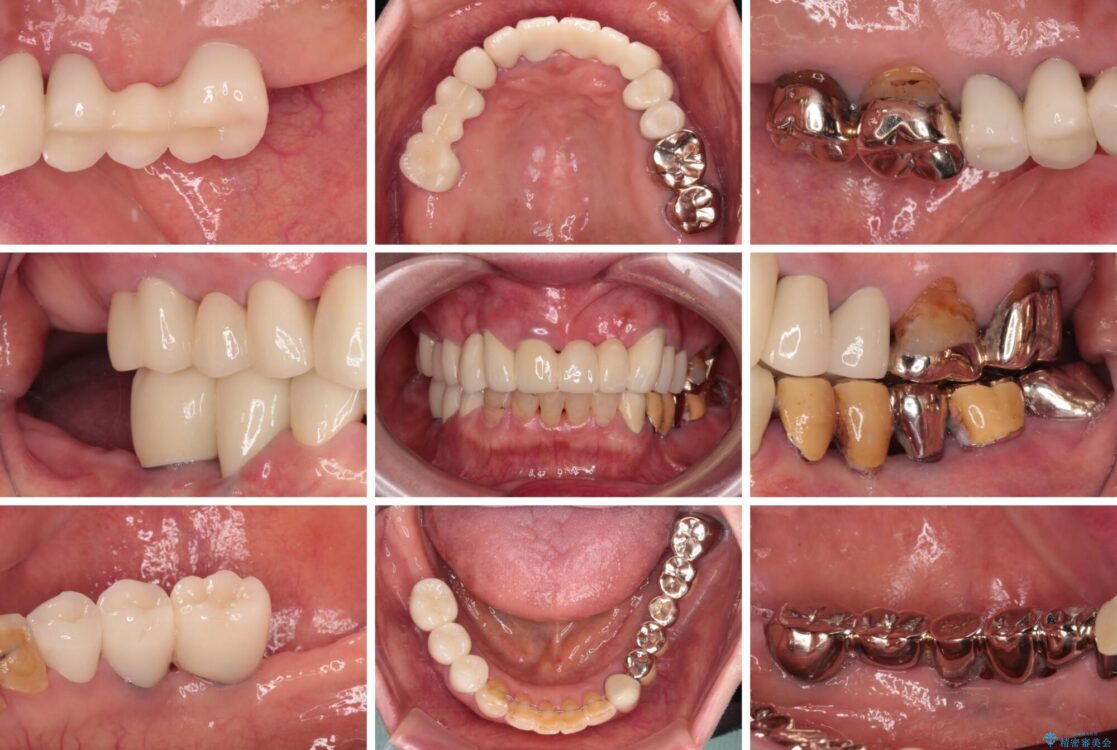

治療前

• 前歯をきれいにしたい インプラントや部分矯正を用いた総合歯科治療 治療前画像

治療後

• 前歯をきれいにしたい インプラントや部分矯正を用いた総合歯科治療 治療後画像